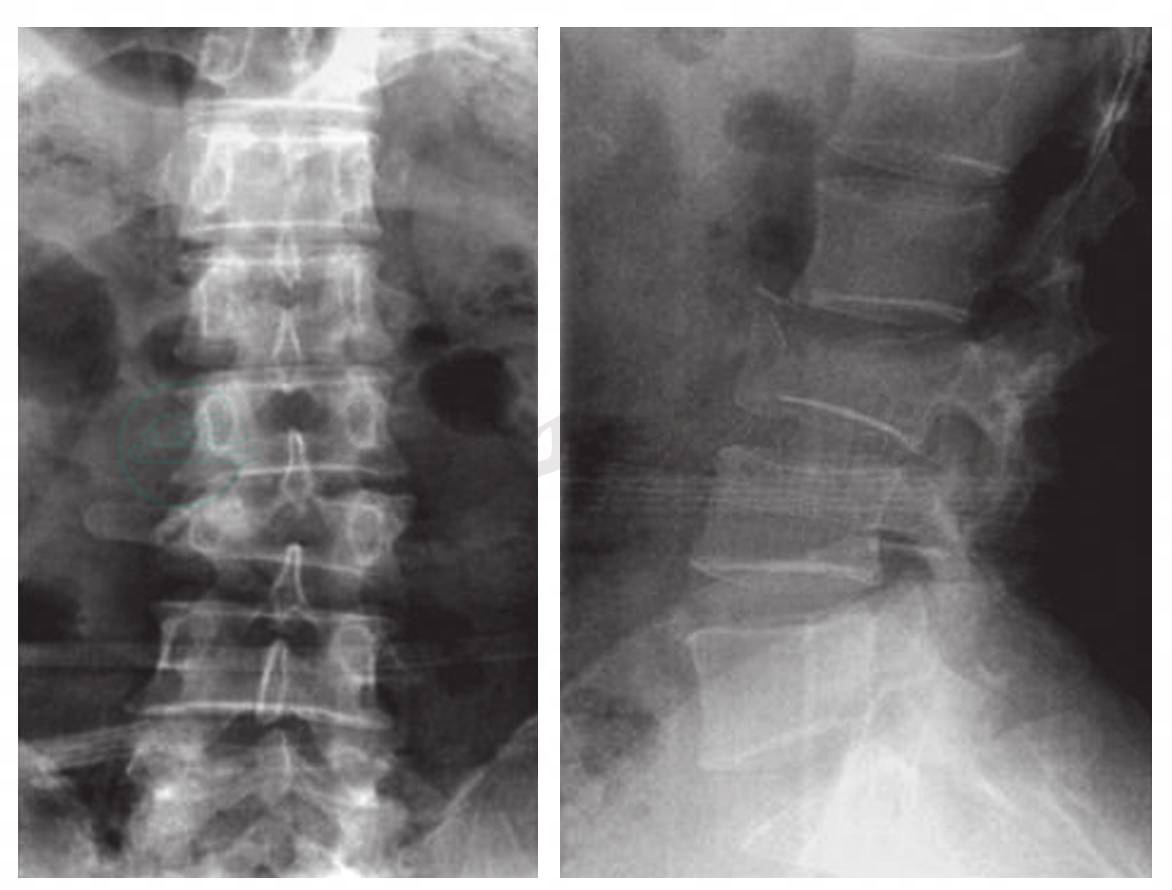

图3-1-5-7 病例1,AO B2.3型T12骨折

A.正位X线片;B.侧位X线片